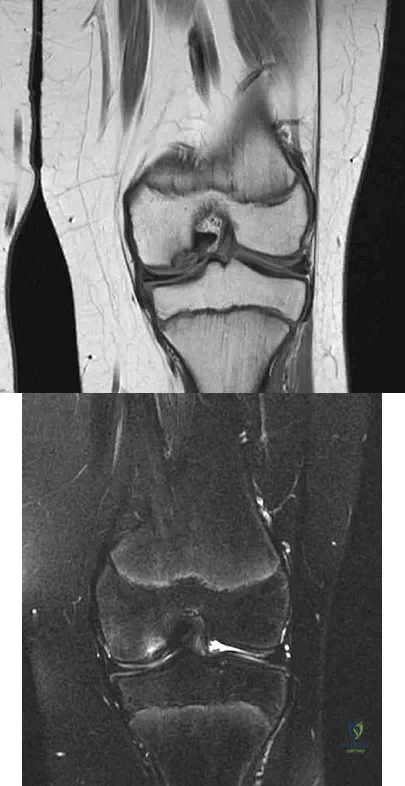

A 12 1/2-year-old boy reports intermittent knee pain and limping that interferes with his ability to participate in sports. He actively participates in football, basketball, and baseball. He denies any history of injury. Examination shows full range of motion without effusion. Radiographs reveal an osteochondritis dissecans (OCD) lesion on the lateral aspect of the medial femoral condyle. MRI scans are shown in Figures 14a and 14b. Initial treatment should consist of

Explanation